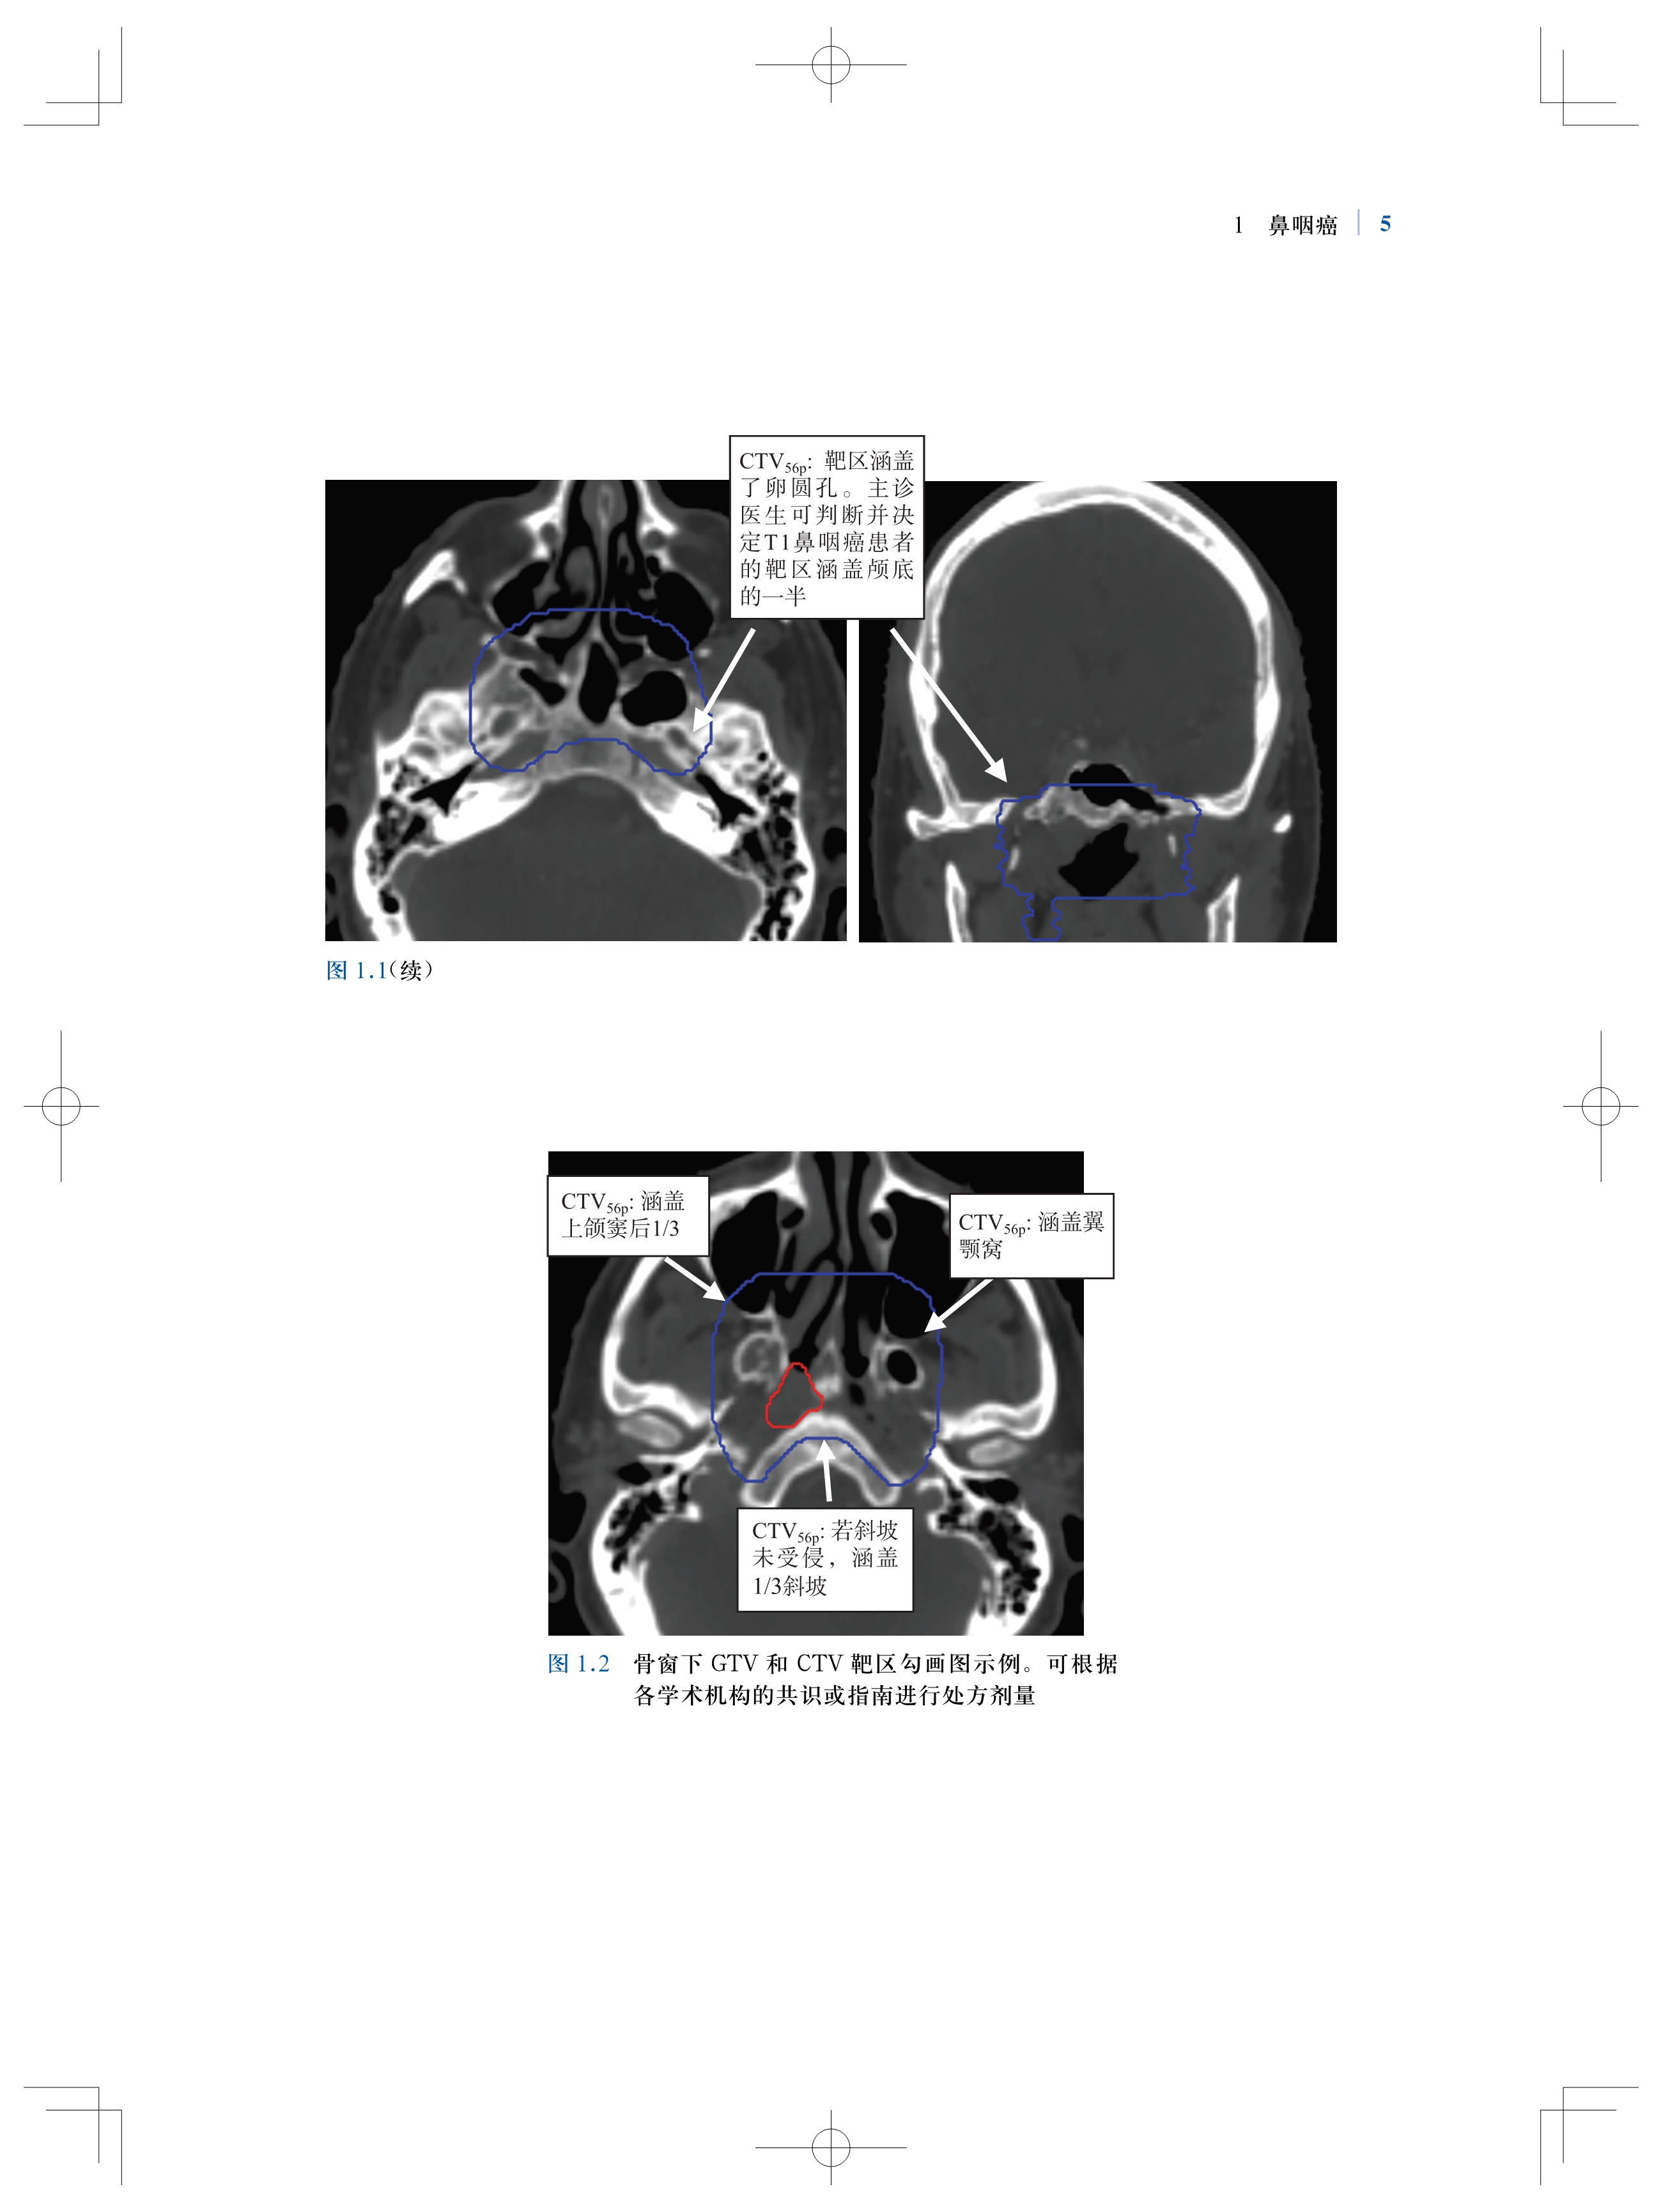

书名:肿瘤放射治疗靶区勾画与射野设置:适形及调强放射治疗实用指南(原著第2版)